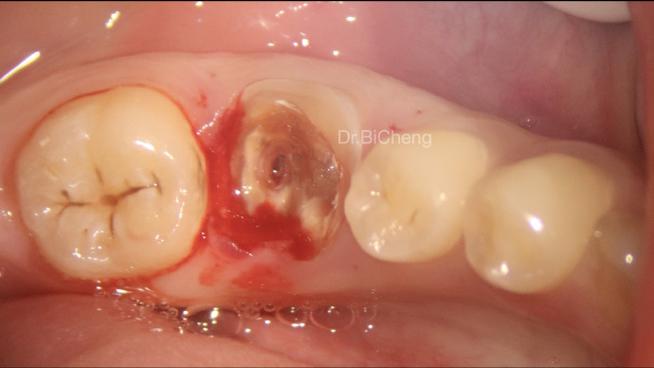

手术流程需严格遵循无菌原则和精准操作,通常分为术前准备、取骨、移植及种植体植入四个阶段,术前评估是基础,通过CBCT三维成像测量缺牙区骨高度、宽度及密度,判断骨缺损类型(垂直缺损、水平缺损或复合缺损),同时检查供区骨量及健康状况,取骨操作中,颏部取骨需沿下颌外斜线做切口,剥离骨膜后显露颏部外板,用超声骨刀截取所需大小骨块,注意保护颏神经;髂骨取骨则需在髂嵴做弧形切口,显露髂骨内外板,根据需要取骨块或骨颗粒,移植阶段,将获取的骨块修整成与受区匹配的形状,用钛钉或钛板固定于缺牙区骨面,确保与周围骨紧密贴合;若采用骨颗粒移植,则需与自体血液混合后植入,覆盖可吸收胶原膜防止软组织侵入,种植体植入可在自体骨移植同期进行(即刻种植),也可在骨愈合3-6个月后延期植入,前者可缩短治疗周期,但对初期稳定性要求较高,后者则需二次手术,但骨整合更充分。